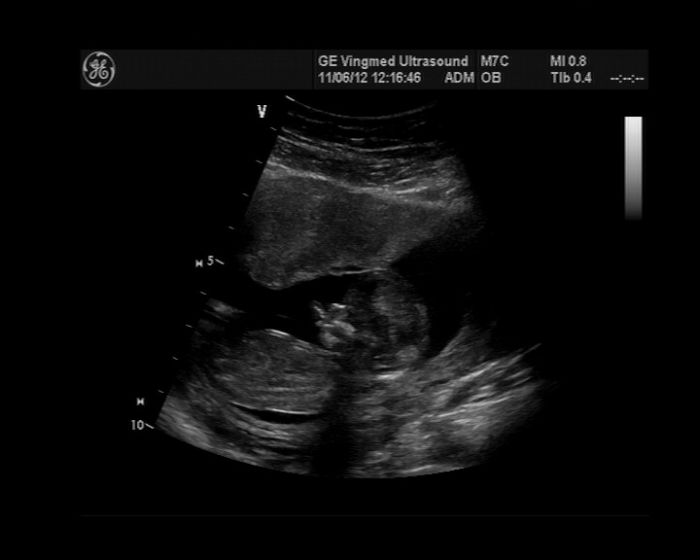

Ahoj, krásný fotečky. Tak přidávám taky jednu

Jana: Jéé to je krásný snímeček, vážně krásné :)